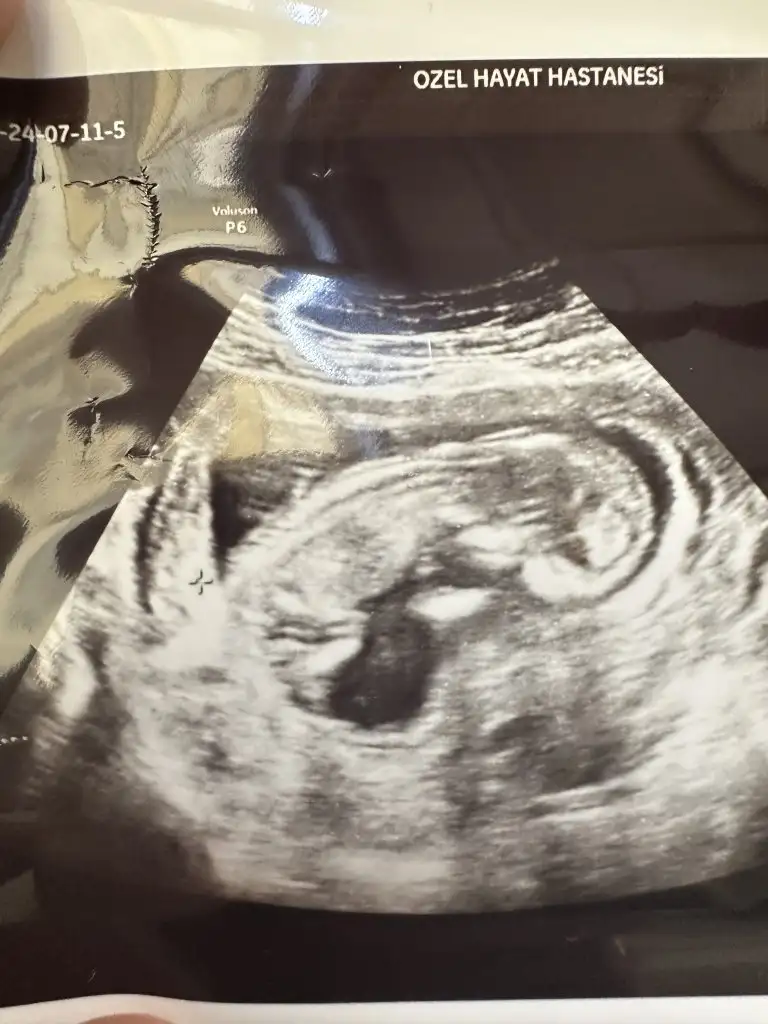

Tahminin doğru çıktı kesinle kız mış kızım olacak mış yanılma olur mu diye sordum 15+6 hafta bu haftadan sonra yanılma olmaz dedi hiç çıkıntı yok bacak arası boş dedi eli ile de gösterdi :)

Kız bebek bacak arası boş 😍